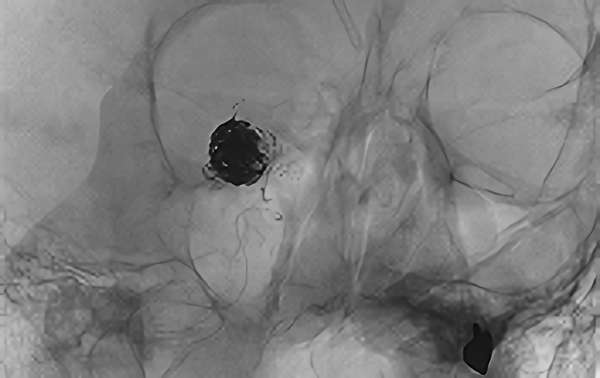

'26年4月

左椎骨動脈後下小脳動脈分岐部動脈瘤

70代

院内外来

No.1628 手術前

No.1628 手術中

No.1628 手術後